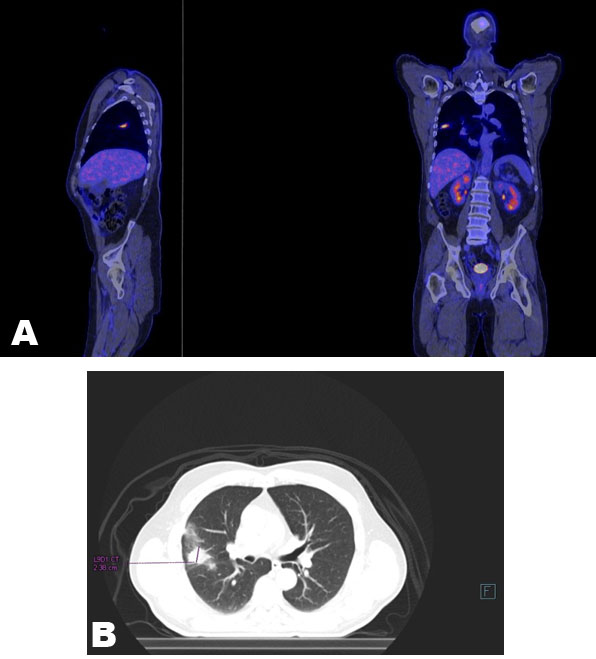

The suspicious lung nodule was further worked up with a bronchoscopy with biopsy. There was notable distortion in the right middle lobe, however, the transbronchial brushings and right middle lobe lavage did not reveal any malignant cells or infection (Figure 3). To exclude pulmonary malignancy, a positron emission tomography (PET) scan was conducted (Figure 4). The spiculated lesion was detected in the posterior segment of the right upper lobe with an increased tracer uptake with a maximum standardized uptake value (SUVmax) of 11.71, which was highly suspicious for malignancy. A repeat CT-guided biopsy was performed in the right upper lobe and the histopathological assessment identified mixed chronic active inflammation with an aggregate of filamentous microorganisms with sulfur granules of Actinomyces and no malignant cells (Figure 5) and (Figure 6).

Figure 4: PET scan. (A) Sagittal, (B) Coronal and transverse view of PET scan showed spiculated lesion in the posterior segment of the right upper lobe is identified. This has moderately increased tracer uptake with an SUVmax of 11.71. There is associated ground glass opacity extending to the adjacent pleura.